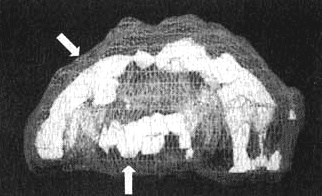

Мозг Уилли — травма головы

Трехмерное изображение — активный мозг, вид сбоку. Обратите внимание на выраженное повышение активности в поясной системе и в левой височной доле (см. стрелки).